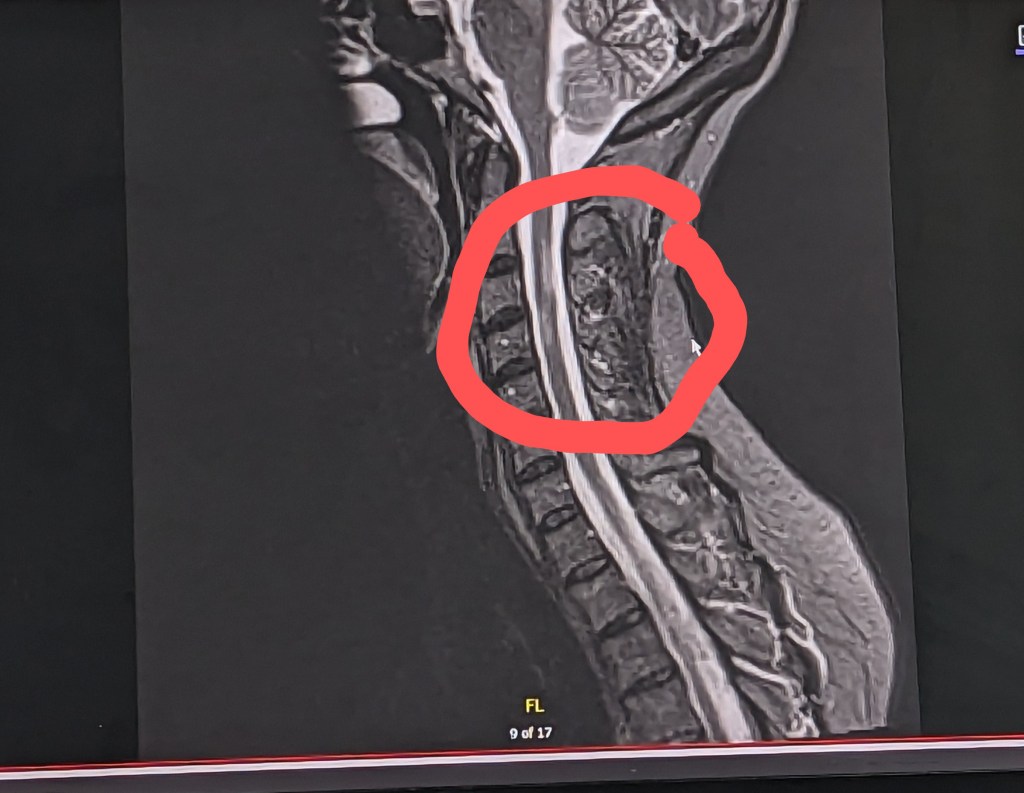

Another new in-patient neurologist looked at my MRI films and loudly stated, “Wow, with all those lesions on your cervical spine, I’m amazed you can walk at all.” I replied back, “Wow, what a supremely unhelpful and hurtful thing to say!” He was appropriately apologetic at his outburst. I suggested he think before he speak next time because his words were incredibly damaging to my tenuous hope and mental stability.

Images above are my brain. The red circle represents one of my very few brain lesions. The image on the left maps water movement throughout my brain.